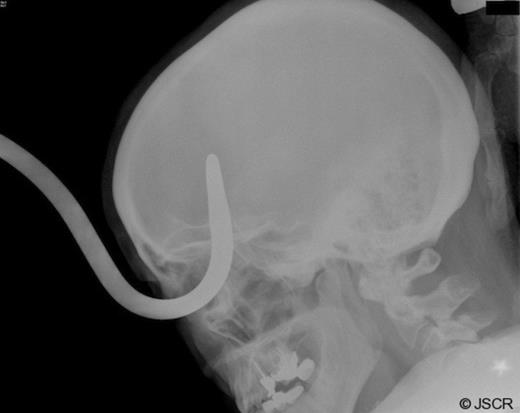

Upon removal of the hook, the patient was taken immediately to the CT scanner for a CT angiogram of the head. The CT scan demonstrated some leftward deviation of the anterior cerebral arteries, but there was no evidence of vascular injury or active hemorrhage. There was evident some recent parenchymal and subarachnoid hemorrhage with small subdural hygroma over the right frontal convexity. There was also hemorrhage and edema of the inferior orbit with displaced medial right orbital wall fracture. The globe was slightly dysmorphic, although the lens was intact, and there was no gross evidence of intraocular hemorrhage. The right orbit extruded such that 75% was beyond the orbital rim (Figure 4). A repeat CT scan was obtained two hours later which demonstrated no change and that the injury was stable.